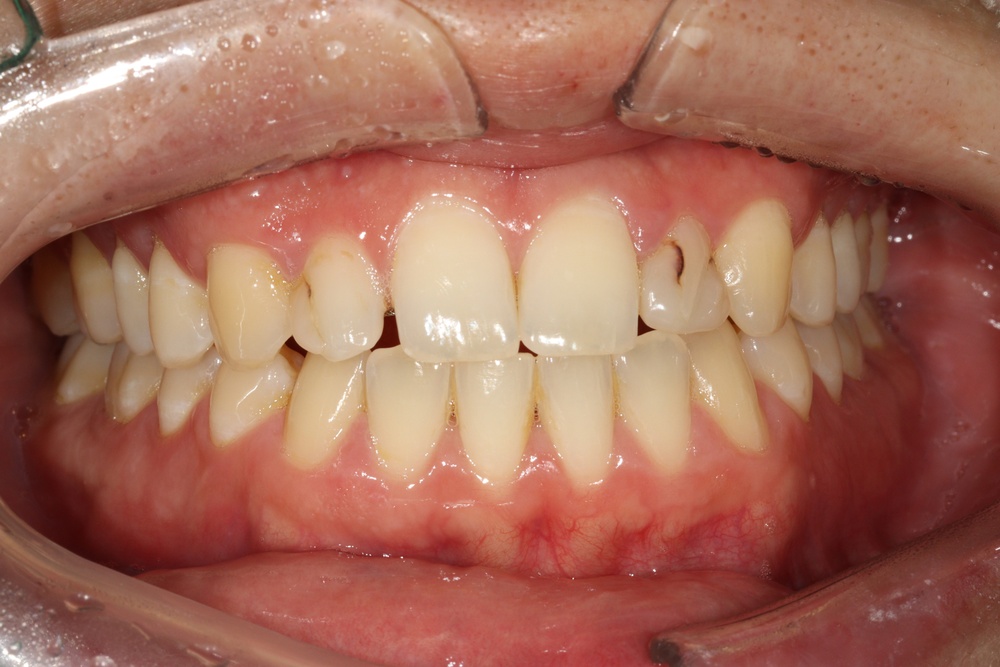

40대의 환자분으로, 앞니가 비뚤어서 코로나가 끝났을 때 마스크를 벗고 웃고 싶다고 하셨습니다.

충치가 많아서 교정 전 충치치료를 전반적으로 시행하고, 잇몸치료도 진행하였습니다.

중년기 교정에서 발생가능한 문제점(치아 사이 틈 발생가능성, 잇몸질환)충분히 설명드리고 시작하였습니다.

치아 배열이 거의 완성된 상태로 치료 전 말씀드렸던 치아사이의 틈(블랙트라이앵글)이 있습니다.

환자분과 상의 후 위쪽은 벌어진 공간을 레진으로 메꾸기로 하였습니다.

치아가 가지런해졌고, 윗니 치아 사이의 틈도 메꿔졌으며, 치아에 있던 충치도 모두 치료하였습니다.